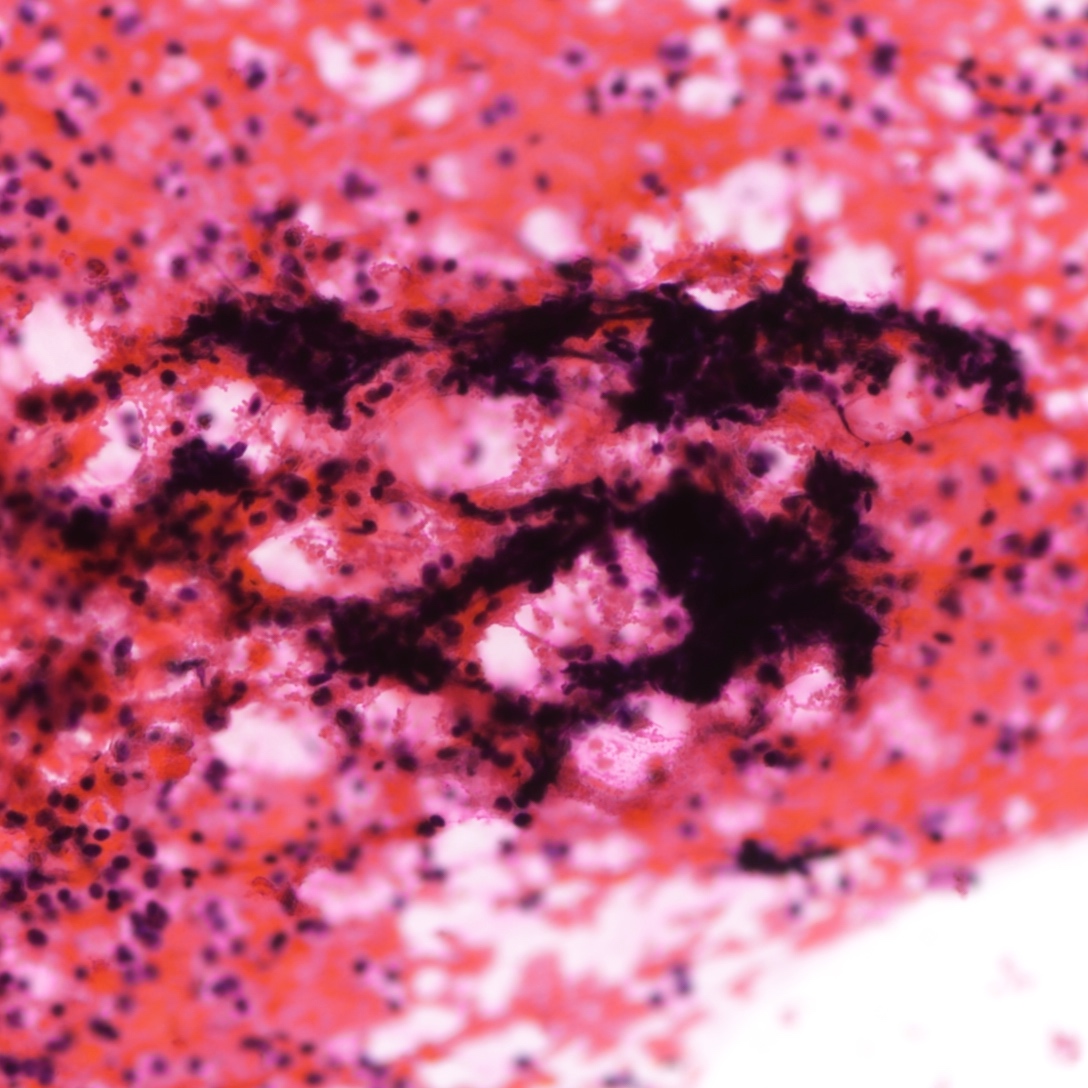

Cytology description

- Neuroendocrine features, including nuclear molding and fine salt and pepper chromatin, may be identified in small cell carcinoma

- Necrosis can be present in the background (J Cytol 2011;28:91)

- Smear preparation can accentuate crush artifact

Cytology images